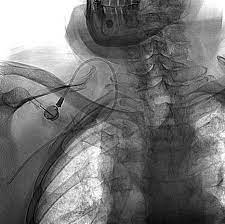

Accesos vasculares: inserción de catéter diálisis